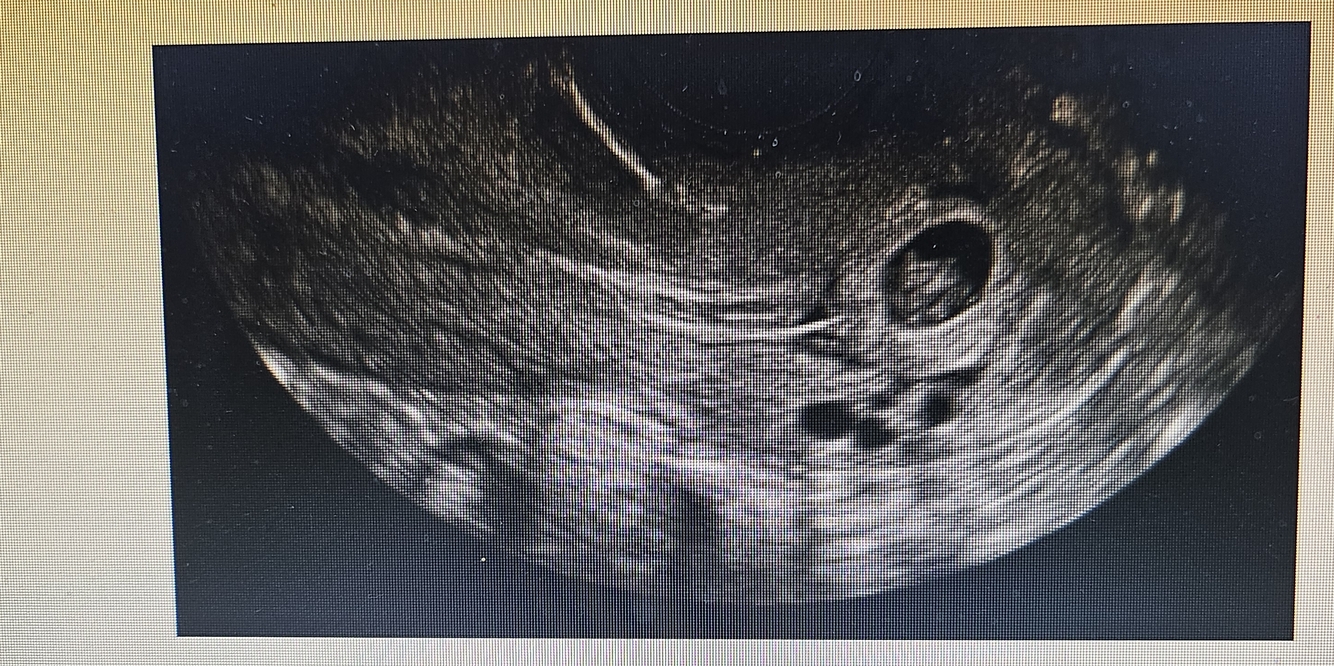

Paciente com dor e sangramento vaginal, USG transvaginal em anexo. Diagnóstico e conduta?

Aborto em curso, realizar esvaziamento uterino com curetagem ou esperar expulsão espontânea